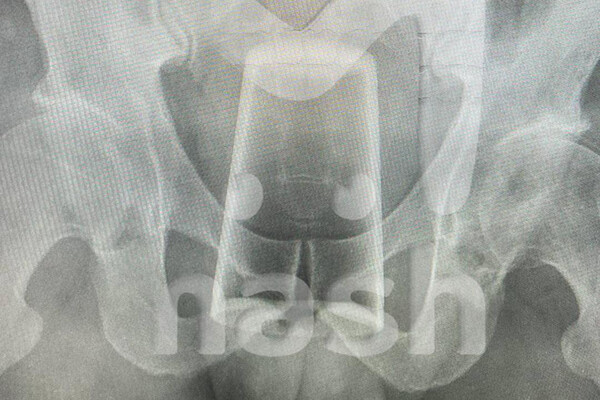

В Уфе мужчина попал в больницу со стаканом в заднем проходе после конкурса на 23 февраля. Об этом сообщает Telegram-канал Mash. Инцидент произошел в День защитника Отечества, когда двое друзей отмечали праздник. По словам пострадавшего, они с товарищем выпили, закусили и решили устроить конкурс. Однако в какой-то момент он поскользнулся и нечаянно упал на стакан, после чего тот оказался у него в заднем проходе. Попытки самостоятельно вытащить инородное тело не увенчались успехом — пострадавшему вызвали медиков. Позже врачи извлекли стакан из заднего прохода мужчины и отпустили его домой, порекомендовав регулярно наблюдаться у специалистов после случившегося. Ранее уфимец два дня ходил со стаканом в заднем проходе, пока не лопнуло стекло.

Попытки самостоятельно вытащить инородное тело не увенчались успехом — пострадавшему вызвали медиков. Позже врачи извлекли стакан из заднего прохода мужчины и отпустили его домой, порекомендовав регулярно наблюдаться у специалистов после случившегося.